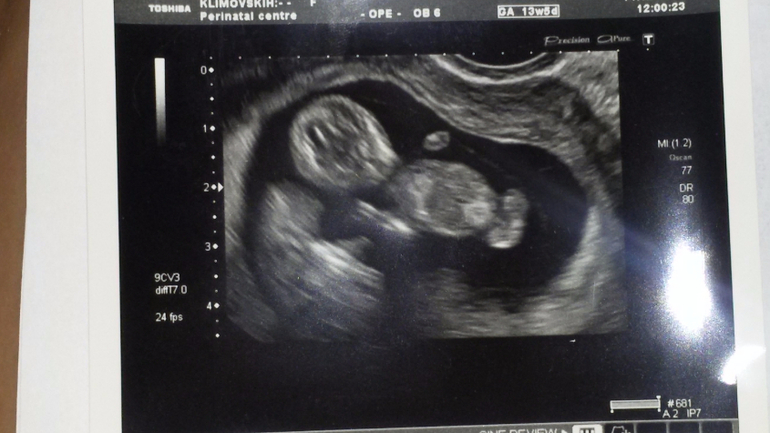

2 декабря... вот дата с которой начало меняться все в моей жизни: зав отделением на узи с точностью разглядела двоих крошек. Две маленький горошинки на одной плаценте (тогда еще ж.мешочке) и в одном пузыре. Монохориальная моноамниотичская двойня прозвучало как приговор, объяснения как опасна и такая беременность и какой процент смертности и замерших беременностей при моно-моно и тут же вопрос: сохраняем?

вот такими я их видела посл раз в 20 недель...